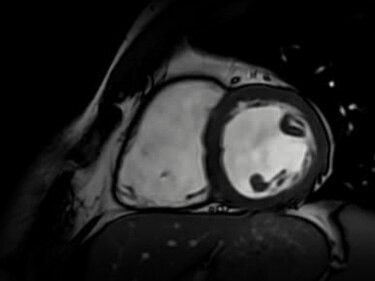

AI-Enhanced cardiac MR

Perform quantification and mapping with revolutionary deep learning

Life-Speed imaging

Achieve up to 12X acceleration and up to 83% scan time reduction*